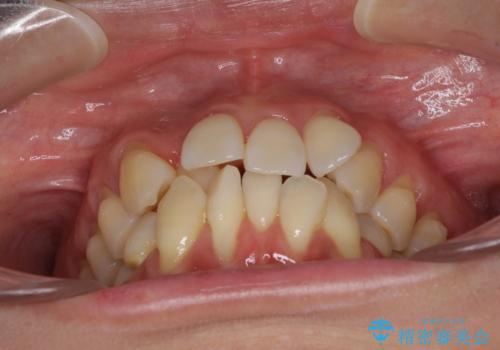

- 上下前歯のでこぼこを気にされ、矯正治療を希望された患者様です。

費用を抑えるため、メタルブラケットを採用し、抜歯矯正を行うこととしました。

通常であれば、上下顎左右小臼歯各1歯の合計4本を抜歯しますが、歯肉退縮の著しい下顎前歯を抜歯して欲しいという患者様の強い希望により、上顎のみ左右小臼歯2歯を、下顎は前歯を1歯を抜歯することとしました。

抜歯する歯を変更したため奥歯の咬合はアンバランスとなりましたが、前歯は綺麗に整い、歯肉退縮も回避できました。